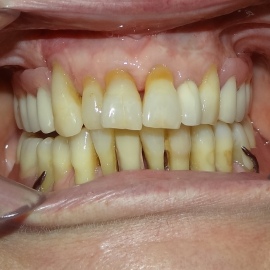

Po utracie zęba w przednim odcinku łuku zębowego należy zwrócić wzmożoną uwagę na aspekt estetyczny. Naczelnym przesłaniem odbudowy brakujących tkanek (anatomiczno-funkcjonalny kompleks tkanek: kość wyrostka zębodołowego + dziąsło + zęby) jest uzyskanie takiego wyniku, który jest najbliżej ideału, czyli takiej sytuacji jak gdyby nic się nie stało i w ogóle nie doszło do utraty zęba i tkanek około zębowych. Kluczem do sukcesu jest odtworzenie poprawnych stosunków anatomicznych: kość - dziąsło - ząb.

Korona protetyczna na implancie, funkcjonująca od roku 2003. Zdarzył się wypadek motocyklowy. Widzimy klucz do osiągnięcia sukcesu: mikrochirurgia i poprawna anatomiczna odbudowa tkanek. Tego nie zastąpi nawet najdroższy implant!